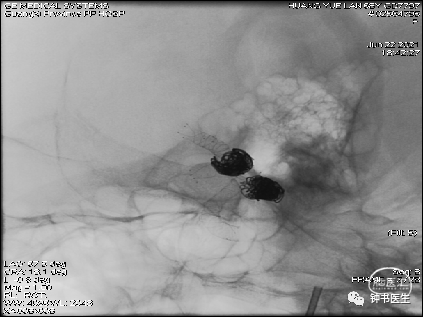

2021-07-05 DSA

Tubridge 4045

TB植入后动脉瘤即刻不显影。